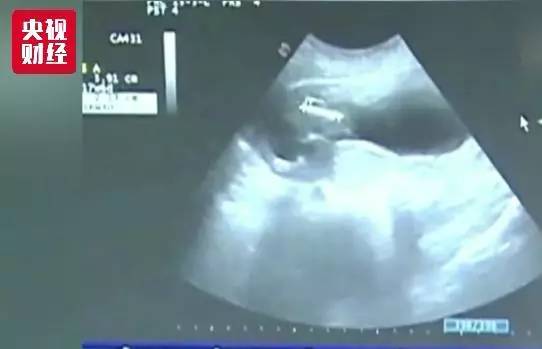

宫颈癌目前已成为女性第三大高发癌症。我国每年宫颈癌的新发病例也在逐年上升,从2005年报告每年十万,上升到了2013年的十五万。如何有效预防宫颈癌,一直为大家关注。

专家介绍,一般宫颈癌疫苗,分为二价、四价、九价,这次获准在内地上市的,是葛兰素史克的HPV二价疫苗。研究显示,人乳头瘤病毒也就是HPV病毒有130多种亚型,而二价疫苗,就是针对HPV病毒的两个最高危亚型的疫苗,能预防70%左右的宫颈癌。